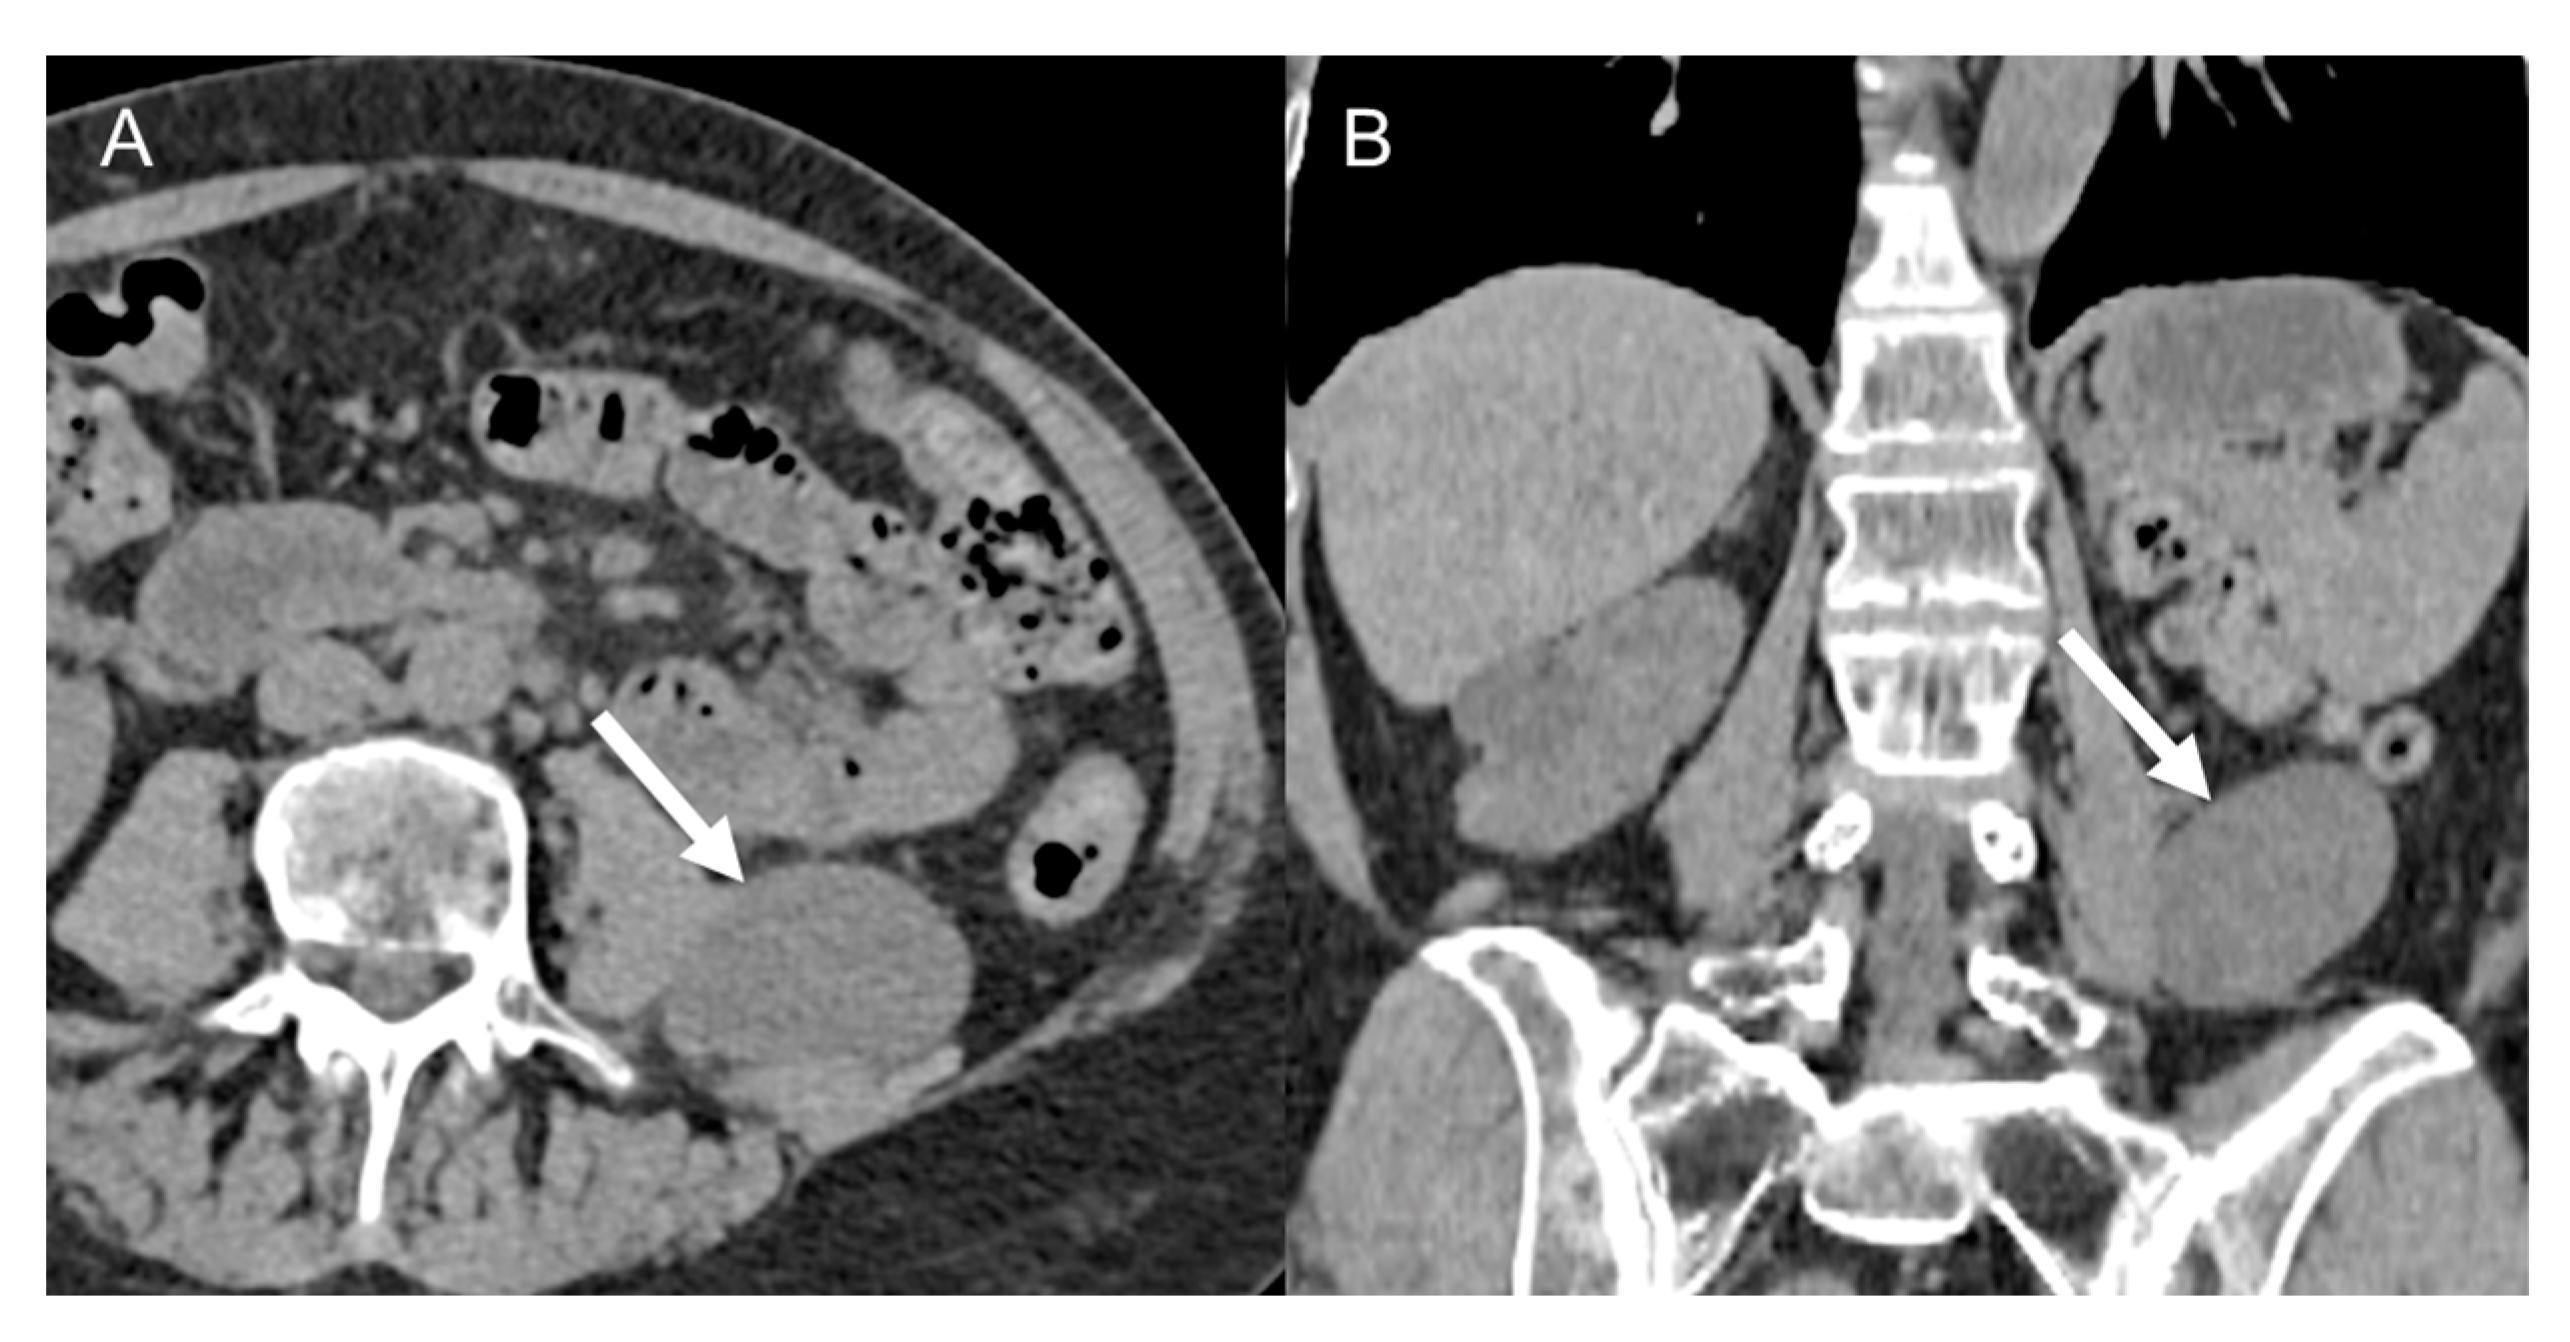

- Well-differentiated liposarcomas (Figure 1) are low-grade tumors. Characteristic CT features include macroscopic fat in at least 75% of the whole tumor with smooth and lobular margins, thick septa (>3 mm), tendency to be nodular, and mild or inconstant low enhancement [5,37,38,39,40]. Calcifications are rare [34] and can indicate dedifferentiation or inflammation. These tumors can recur, but do not tend to metastasize [5].

Figure 1. Well-differentiated retroperitoneal liposarcoma in a 71-year-old man. Axial (A) and coronal (B) contrast-enhanced CT images in the venous phases show a 13.3 cm fat-attenuating mass adjacent to the left psoas muscle, with thin septa (arrow). The lesion was histologically confirmed after surgical excision.

- Dedifferentiated liposarcomas (Figure 2) are high-grade tumors with poor prognosis. Characteristic features include heterogeneous nonlipomatous mass within, adjacent to, or surrounding a fatty mass [37,38]. There may be no evidence of fat-density tissue in up to 20% of cases, making the imaging diagnosis difficult [40]. Enhancing septa within the fatty portions are frequently seen [37]. Calcifications are rare (around 25% of cases) and are poor prognostic factors [39].

Figure 2. Dedifferentiated retroperitoneal liposarcoma in a 68-year-old man. Axial (A) and coronal (B) contrast-enhanced CT images in the venous phases show a 24 cm solid mass in the right retroperitoneal space, with internal necrotic areas and adjacent nodules (arrows). The lesion was histologically confirmed at biopsy.